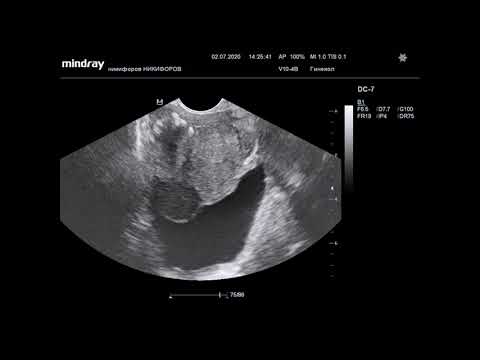

Простатит – общее название заболеваний предстательной железы, имеющих воспалительную природу. Простатиты могут быть вызваны самыми разными факторами – инфекцией (грибковой, протозойной, вирусной, бактериальной), аллергией, застойными процессами в области малого таза, гормональными изменениями в организме мужчины. При воспалении простата опухает, сжимает мочеточник, утрудняет мочеиспускание. Осложненное мочеиспускание – один из самых выразительных симптомов воспаления железы. При развитом течении воспалительного процесса ткани железы начинаю выделять гной. На мониторе ультразвукового сканера можно все это хорошо увидеть – размер воспаления, закупоренные протоки железы.

- Трансректальный (ТРУЗИ). Этот вид диагностики относится к адресным методам исследования, его используют именно для оценки состояния простаты. Датчик вводят через прямую кишку. Оценка – 95%.

Если обследуемому делают ТРУЗИ, то его кладут на левый бок и вводят ему ректально специальный датчик в форме пальца на глубину 6-8 см. Пациент расположен в «позе эмбриона».

Узкий удлиненный датчик вводится в прямую кишку, предварительно на него одевают презерватив и обрабатывают гелем. Датчик вводится на глубину около 6 см, что позволяет оценить состояние предстательной железы со всех сторон. Продолжительность процедуры составляет около 15-30 минут.